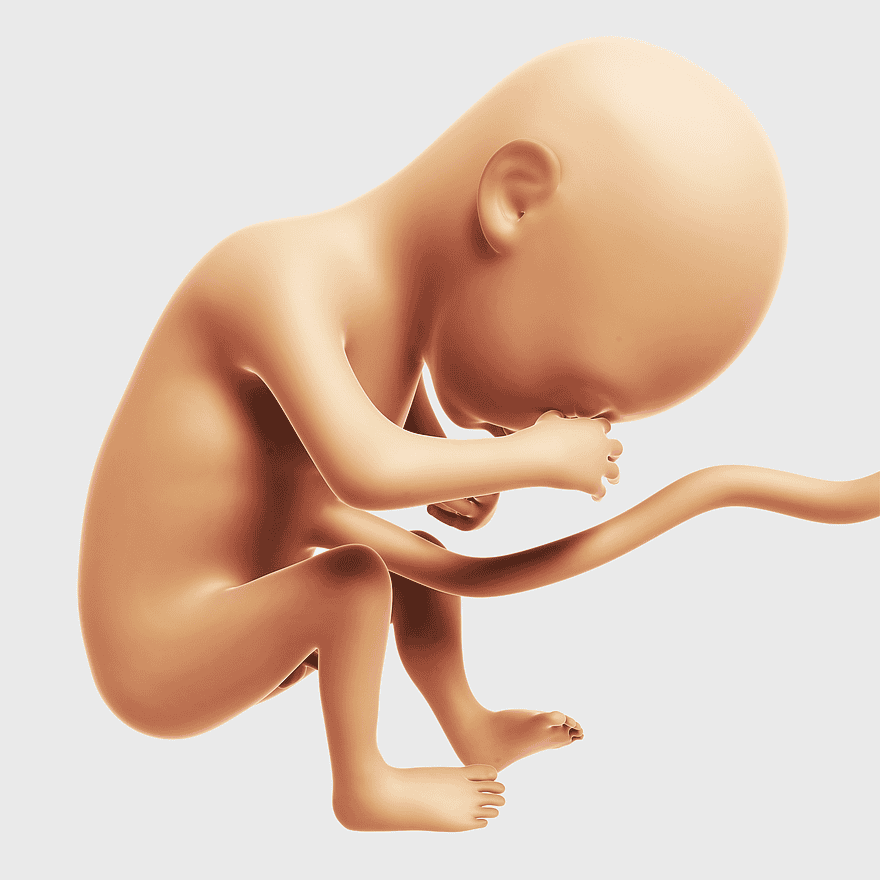

Fetus illustration, prenatal development stages, sleepy baby graphic, umbilical cord depiction, fetal anatomy details, human embryology visuals, pregnancy trimester, PNG

- fetus illustration

- prenatal development stages

- sleepy baby graphic

- umbilical cord depiction

- fetal anatomy details

- human embryology visuals

- pregnancy trimester